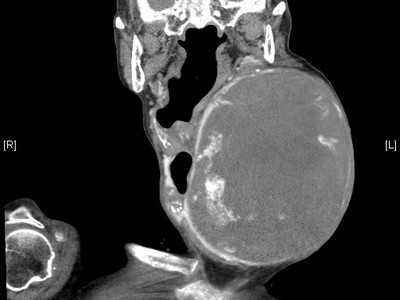

左圖:電腦斷層冠狀切面,顯示術前萬女士脖子上直徑18公分大的巨大甲狀腺腫瘤。

直徑18公分大的巨大腫瘤,對87歲的萬女士來說,脖子上每天都像是揹著顆哈密瓜般的沉重,近期更出現吞嚥困難、喘鳴、昏眩的情況。五月底,長期在各原住民部落進行社區營造的的慈濟基金會慈善事業發展處,於花蓮縣光復鄉發現此個案,立刻轉介花蓮慈濟醫院,由耳鼻喉科周昱甫醫師收治,確診萬女士罹患的「結節性甲狀腺腫」,進行手術治療後,為萬女士摘除重達1.12公斤、最大直徑18公分的巨大良性甲狀腺腫瘤。萬女士術後復原狀況良好,摸著已經光滑的脖子,萬女士開心的說「謝謝花蓮慈院,把我的腫瘤變不見,讓我又可以去教會做禮拜了!」

周醫師表示,萬女士左頸的巨大甲狀腺腫瘤,已嚴重將萬女士的食道與氣管擠壓至右側,出現吞嚥困難、喘鳴的情形;腫瘤甚至壓迫頸動脈導致昏眩的症狀。醫護團隊考量萬女士的喉返神經與頸動脈經已嚴重受到壓迫,未來可能導致聲帶麻痺、半身麻痺、中風等可能性,加上腫瘤影響外觀,造成萬女士社交與心理上的障礙,有手術治療的必要性。雖然萬女士已屆高齡87歲,但是經過心臟超音波等檢查後,確認萬女士除了巨大腫瘤的問題外,身體十分硬朗,與家屬溝通後,決定為萬女士進行腫瘤摘除手術。